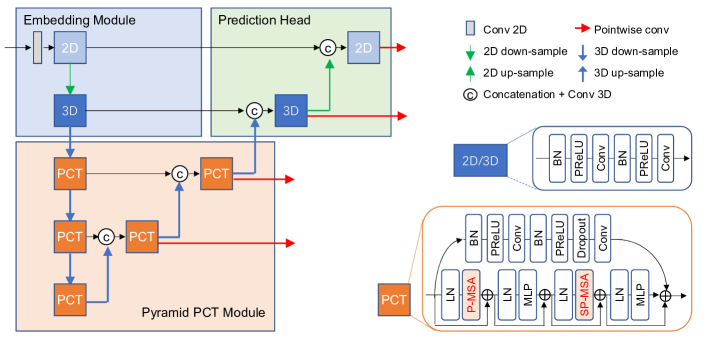

The structure of our proposed PCT-Net is illustrated in Fig. 3. It has three main components: a multi-scale feature embedding module, a pyramid Parallel Convolution and Transformer (PCT) module, and a prediction head. The embedding module uses convolutional layers to extract local features at two resolution levels. Considering that medical images usually have an anisotropic 3D resolution where the intra-plane pixel spacing is lower than inter-plane spacing [43, 50], we use a 2D convolutional block at the highest resolution level, which is followed by a 2D downsampling. After the 2D downsampling, the 3D resolution is less anisotropic, and a 3D convolution block is used in the second resolution level. Each 2D/3D convolution block consists of two basic convolutional layers, with each containing a Batch Normalization (BN), a Parametric Rectified Linear Unit (PReLU) activation and a 2D/3D convolution operation. In addition, before the 2D convolution block, a project layer based on 2D convolution is used to convert the input image to a high-dimension feature map.

The pyramid PCT module has three resolution levels with an encoder-decoder structure equipped with PCT blocks. A PCT block has two branches. The first branch uses convolutional layers to extract local features. It has a structure similar to the 3D convolution block used in the embedding module, and the difference is that a dropout layer is used before the second 3D convolution operation. The second branch consists of two self-attention blocks to learn long-range dependency. Considering the large voxel number in 3D volumes, we use a 3D version of Swin Transformer [25] to reduce the cost of computation and memory, i.e., Patch-based Multi-head Self-Attention (P-MSA) that applies self attention at each of non-overlapping patches instead of the entire volume . The first self-attention block has a Layer Norm (LN), a P-MSA, followed by another LN and a MLP. The second self-attention block is similar to the first one, and it uses a shifted version of the P-MSA (SP-MSA), where the shift size is half of the patch size. The outputs of these two branches in a PCT block are added together so that the complementary local and global features can be leveraged.

The prediction head recovers high-resolution feature maps that is symmetric to the embedding module. At each resolution level, a concatenation with convolution is used to fuse the feature from the embedding module and that upsampled from a lower resolution level, and it is followed by a 2D/3D convolutional block. We use a pointwise convolution to predict a segmentation map at each of the two resolution levels. In addition, two pointwise convolutions are used at the first two resolution levels of the pyramid PCT module respectively, so that PCT-Net generates predictions at four different scales that are used for deep supervision.